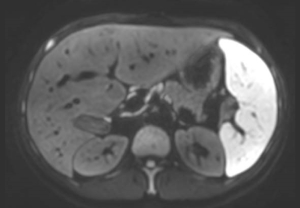

T2w TSE

Ingenia Ambition 1.5T